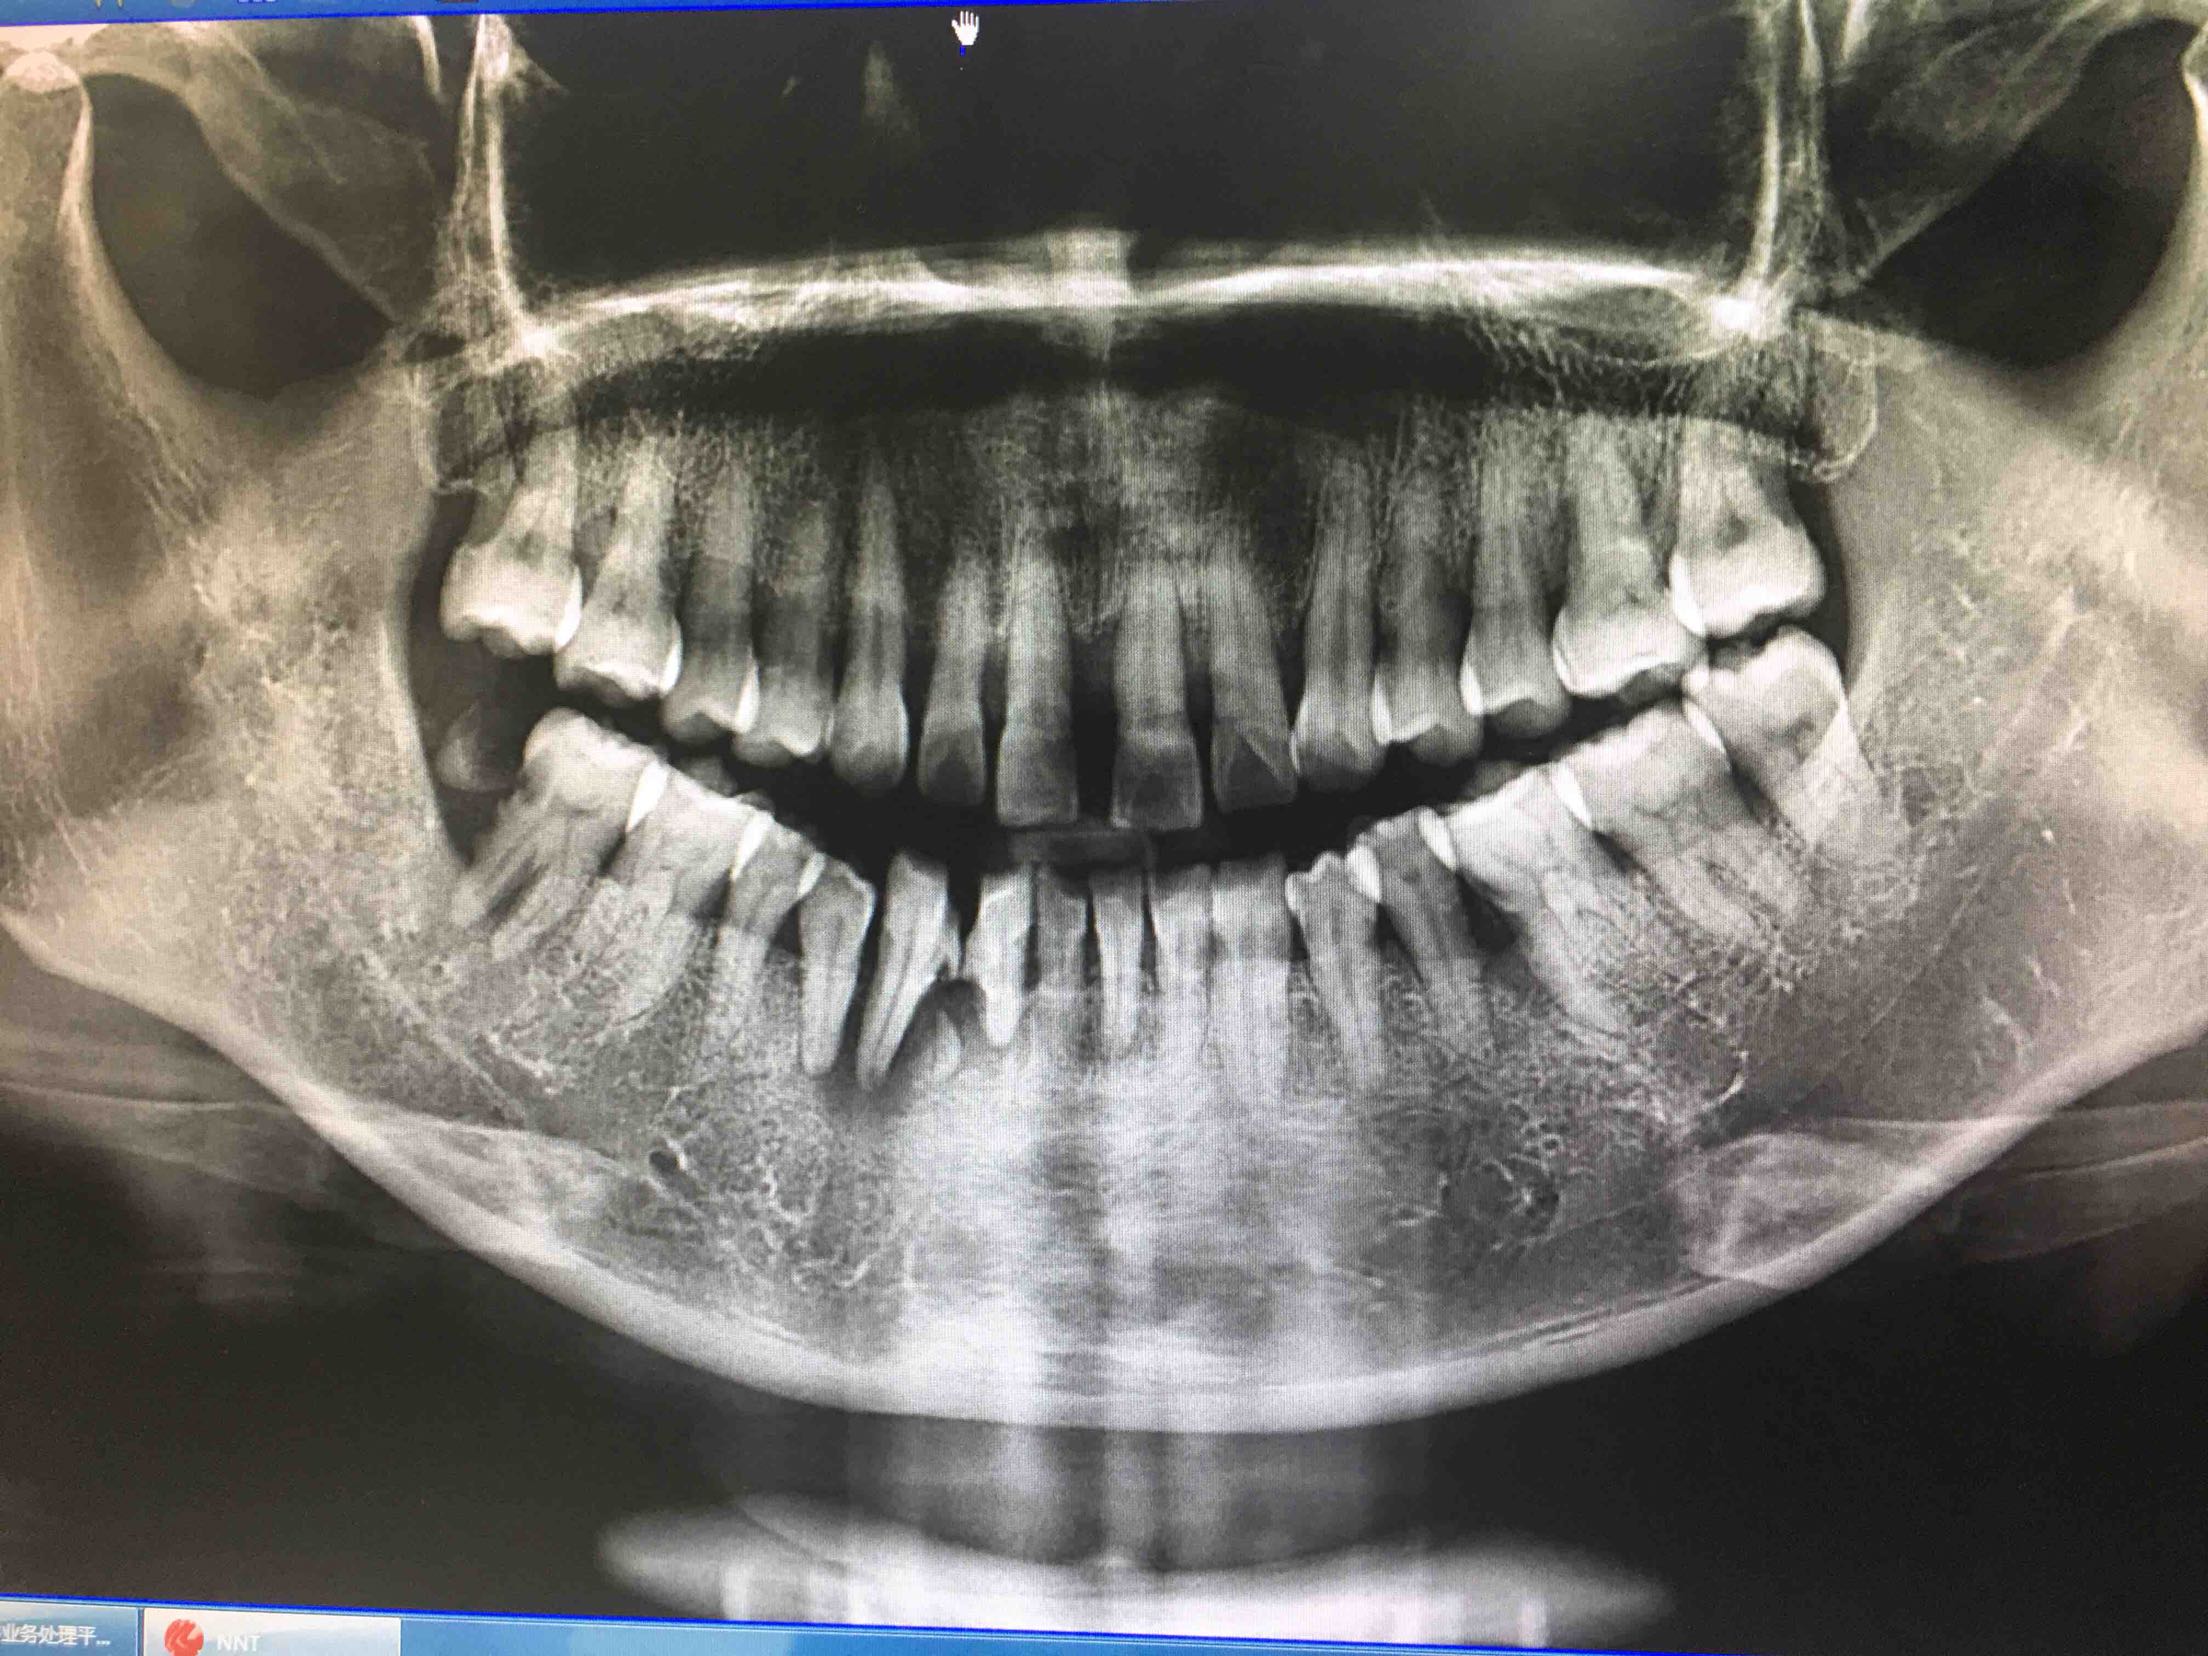

41、43、44牙松动2-3度,42牙缺失,全景片及CBCT显示牙槽骨吸收严重。

拔除41、43牙

两周后,局麻下,翻瓣拔除44牙,在41、42根方环形钻取骨块,钛钉固定于43牙骨缺损处,Bio-ss骨粉0.25g,海奥生物膜,严密缝合!嘱半年后植牙!